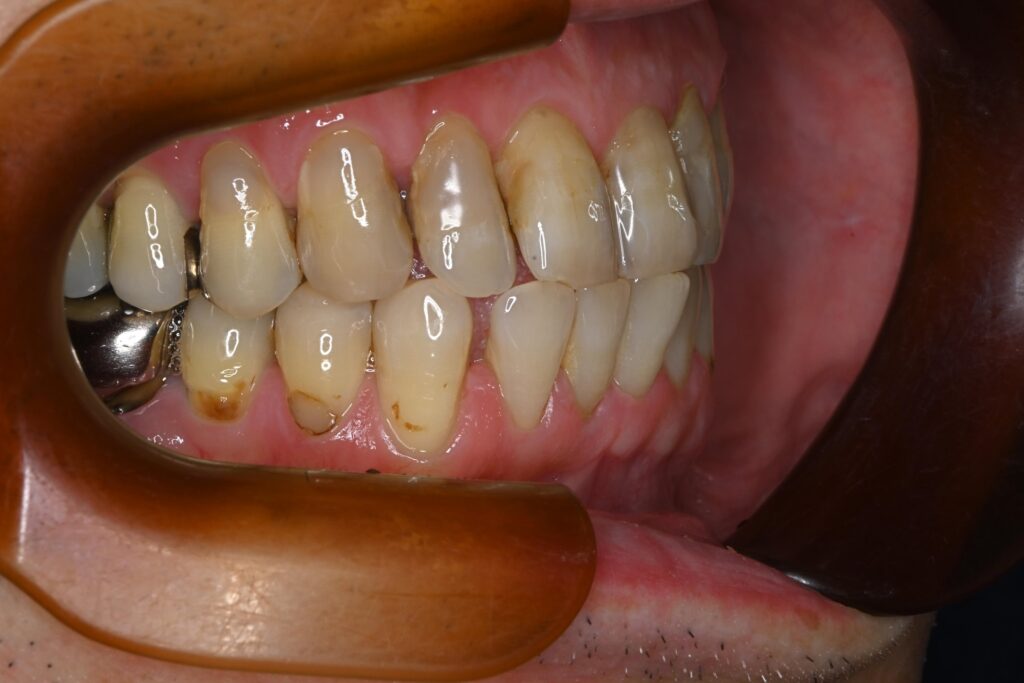

お口全体に虫歯や歯周病の原因となるプラーク(歯垢)が多く付着していました。右上奥歯は重度の虫歯で歯冠部(歯の頭)が失われており、左下奥歯は過去の治療箇所から細菌が入り込み、根の先に炎症が起きている状態でした。

また、左右の奥歯にはWSD(楔状欠損)があり、知覚過敏も見られました。

単なる虫歯だけでなく、「切端咬合(せったんこうごう)」という噛み合わせの不調和が根本的な問題であると診断しました。この噛み合わせにより奥歯に過度な負担がかかり、知覚過敏や歯の損傷を引き起こしていました。

本来は奥歯で受けるべき咬合力が前歯に集中しやすく、前歯の摩耗や欠け、知覚過敏(WSD)を引き起こす原因となることがあります。

また、噛み合わせのバランスが崩れることで、結果的に奥歯や顎関節に負担が及ぶ場合もあります。